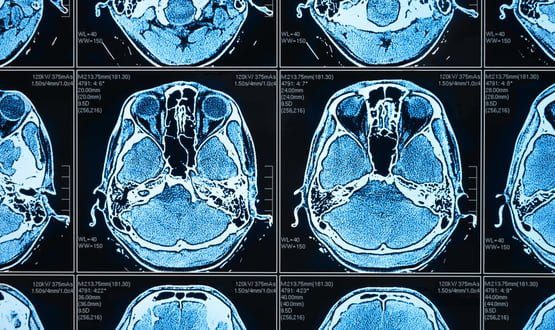

GE HealthCare announced that its Brazil-based partner Ionic Health received FDA 510(k) clearance for its nCommand Lite, which provides diagnostic imaging centers with real-time scanning, remote guidance and operational support, and the ability to…